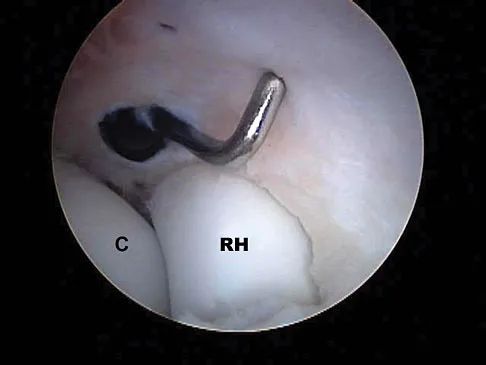

A 30-year-old woman injured her ankle playing soccer 3 months ago. She now reports popping and pain over the lateral side of her ankle. An MRI scan is shown in Figure 33. What structure needs to be repaired to alleviate the popping?

Explanation

The symptoms and MRI scan indicate dislocated peroneal tendons. In this patient, the structure that needs to be repaired is the superior peroneal retinaculum. If the popping was coming from a torn peroneal tendon, repair would involve the peroneal longus or brevis tendon, but this is not shown in the MRI scan. The anterior talofibular ligament or the calcaneofibular ligament would need to be repaired if the patient had ankle instability due to an ankle sprain. Jones DC: Tendon disorders of the foot and ankle. J Am Acad Orthop Surg 1993;1:87-94.